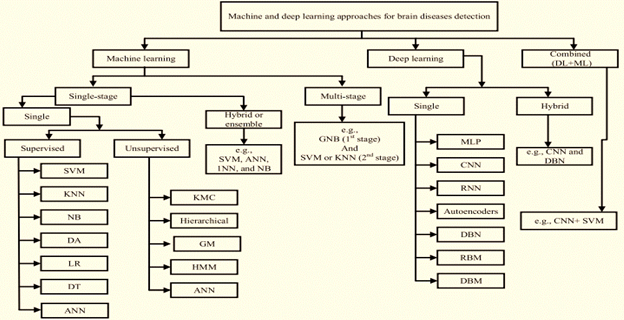

The evolution of ML and DL in the healthcare industry for brain disease diagnosis and detection has many approaches over the time as shown in Figure 5. The distinction between ML and DL from the literature can be seen in the information recognition pattern15 as shown in Figure 6.

Figure 5 Classifications of ML and DL techniques to detect brain diseases.14